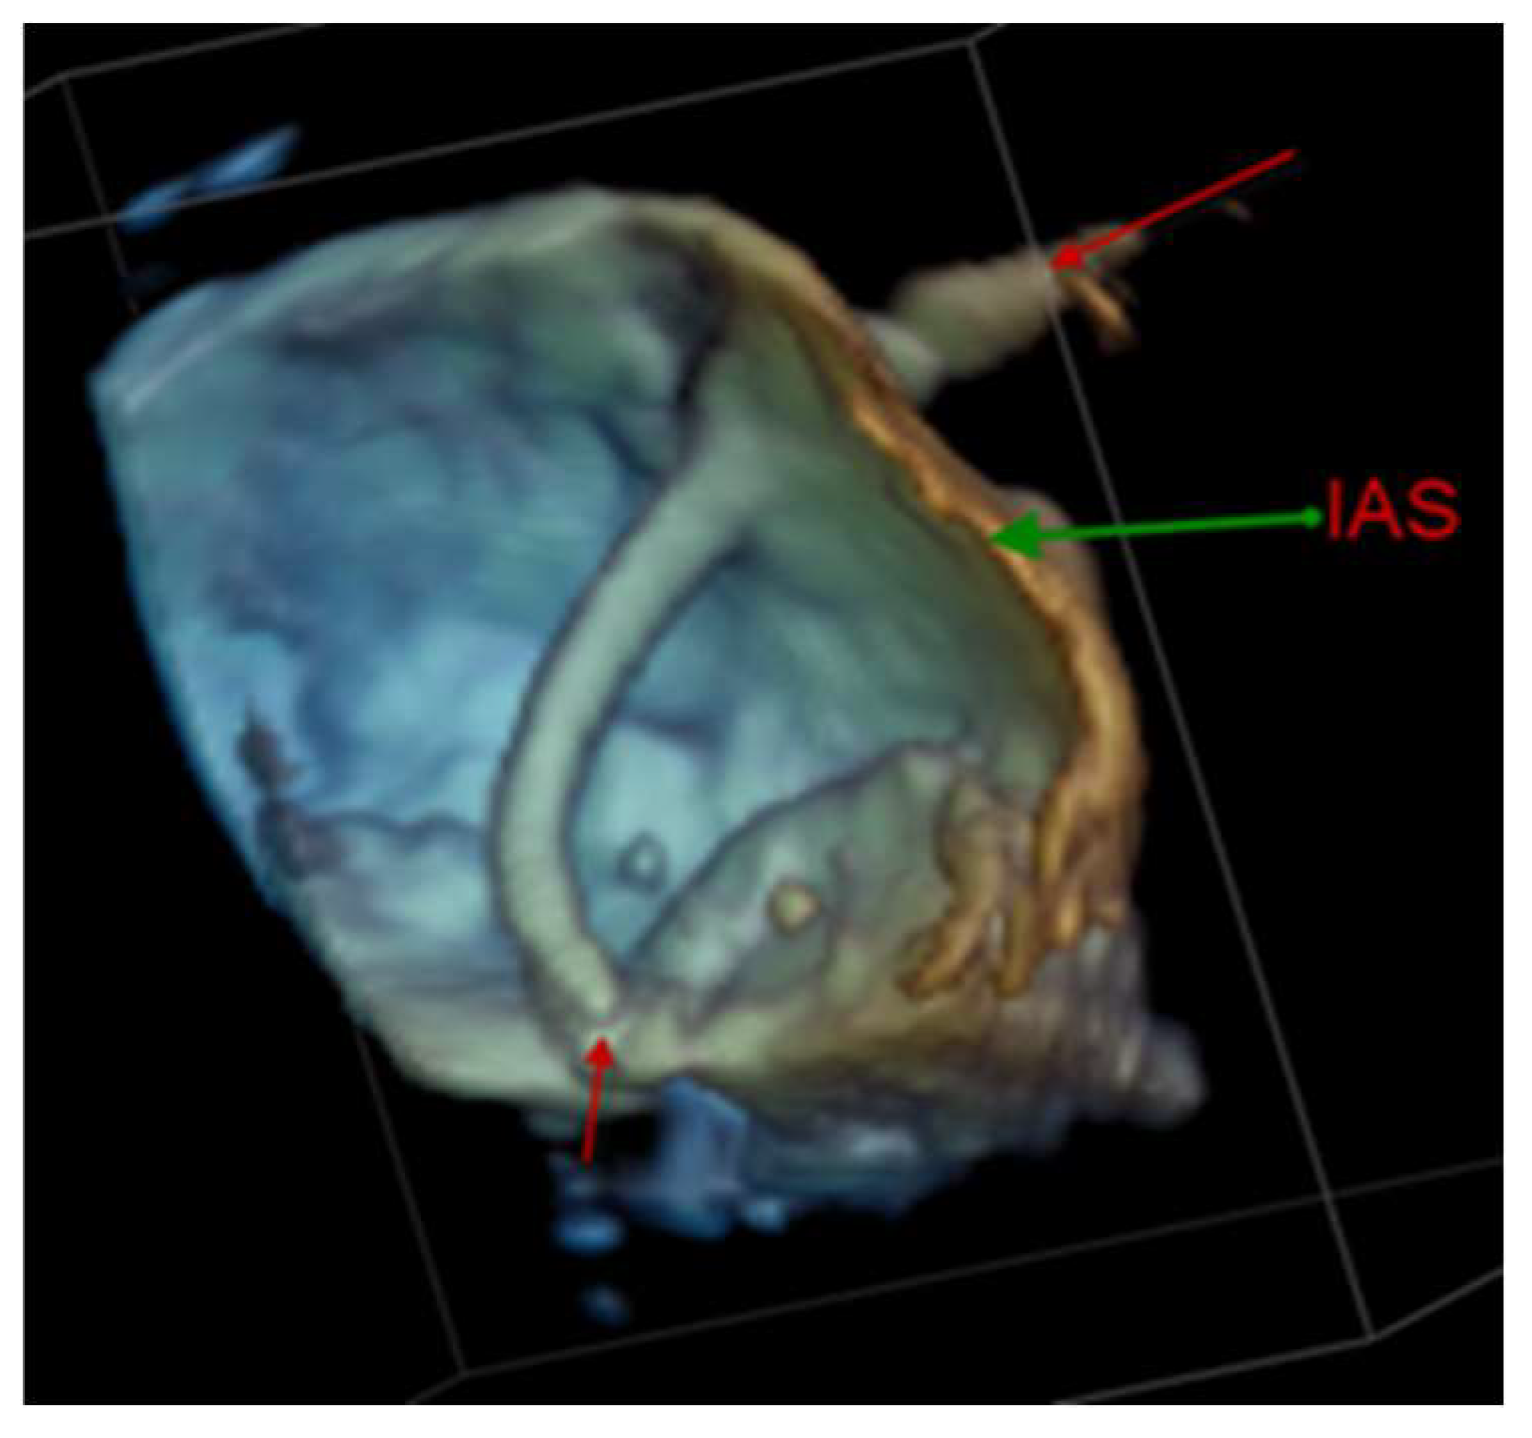

4.2.1. Transseptal Puncture